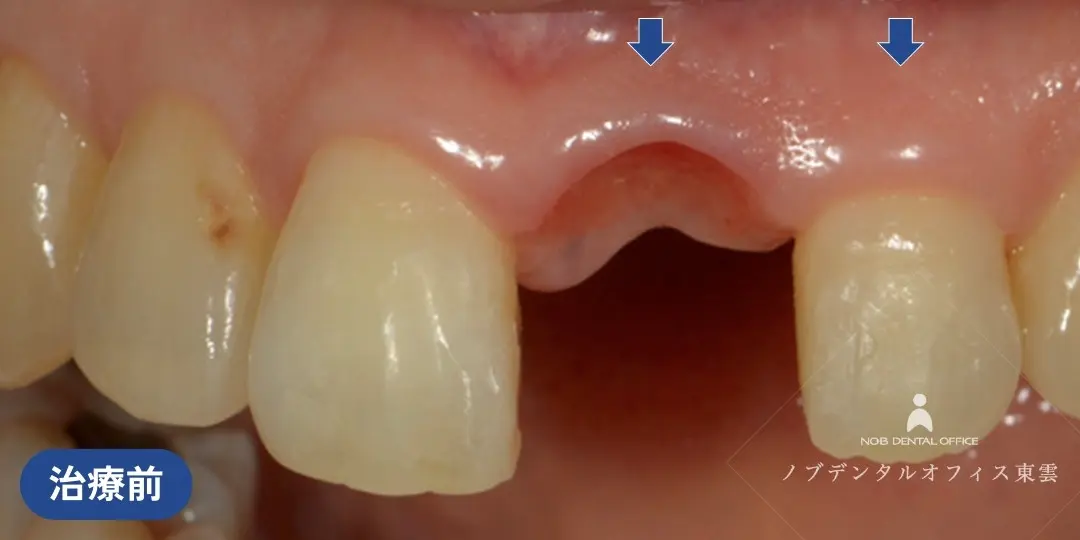

前歯の欠損を接着性ブリッジで治療した症例(60代女性)

上の前歯の歯ぐきが腫れてしまった状態を繰り返していました。

診察の結果、歯根に亀裂(きれつ)があり、残念ながら抜歯が必要との診断でした。

当院で抜歯を行いました。

インプラント・ブリッジ・入れ歯の治療計画をお話しさせていただき、治療期間やリスク、審美性や周囲の歯への負担を考慮して、接着性ブリッジで修復しました。

接着性ブリッジとは、隣の歯の一部のみを削り、貼り付けるタイプの補綴物です。

支台歯の削る量を最小限に済ませ、審美性も高いのが特徴です。

抜歯した状態。治療期間中は仮歯を入れます。

隣の歯の一部のみを削り、ジルコニアを貼り付けています。削る量が少なく負担の少ない治療です。